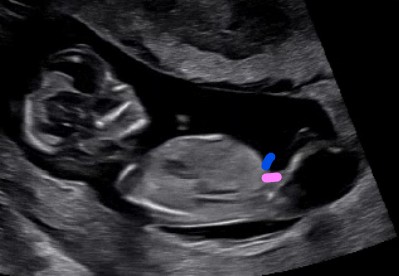

2️⃣ 각도법 (Angle Theory)

임신 12주 이상이 되었을 때 초음파 사진을 활용해 아기의 척추와 생식기의 각도를 보는 방법이에요.

- 수평이면 딸

- 30도 이상 각도가 있으면 아들

👩 로라 1호의 경험: 생식기가 정확하게 찍히지 않았어요😂

다만, 다리사이 사진을 참고해봤는데, 생식기가 보이지 않아 딸인가? 했습니다.

이 시기엔 생식기 발달이 명확하지 않아 16주~18주에 다시 초음파를 보면 많은 반전이 생긴다고도 합니다.